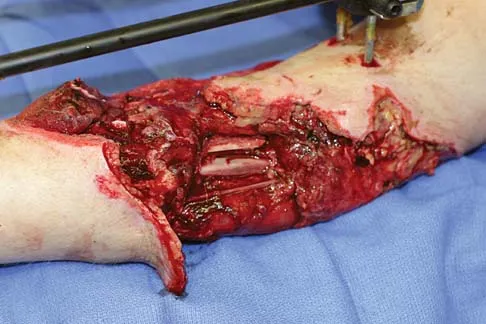

Figures 1a through 1c show the radiograph and MRI scans of a 16-year-old patient who has a painful hip. Examination reveals a significant limp, limited abduction and internal rotation, and severe pain with internal rotation and adduction. A biopsy specimen is shown in Figure 1d. What is the deposited pigment observed in this condition?

Explanation